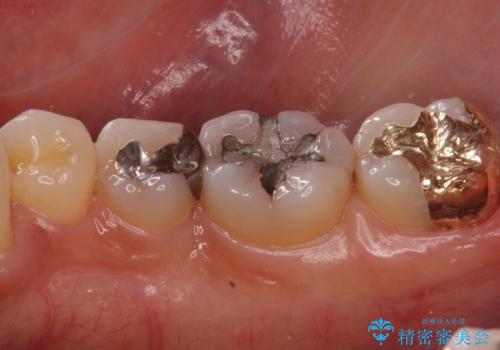

- 右下奥歯が気になるとのことで来院された患者様です。

銀の詰め物の適合が悪く、歯と銀歯の間に歯茎が入り込んできている状態でした。

銀歯を除去し、適合の良いゴールドアンレーで修復していきます。